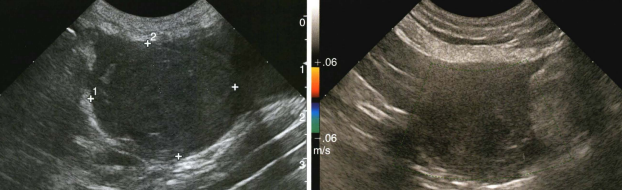

04【超声下表现】 (1)正常子宫影像 (2)子宫残端积液影像 (图片来源:Mattoon, J. S., Sellon, R. K., & Berry, C. R. (2020). Small animal diagnostic ultrasound (4th ed.). Elsevier Saunders.)

05【诊断】 (1)病史:有绝育手术史,之后出现上述症状。 (2)体格检查:腹部触诊可能摸到腹内的团块。 (3)影像学检查: ① 超声:这是首选的、最具诊断价值的方法。可以清晰地看到膀胱附近有一个充满液体的囊状结构(子宫残端),并能评估其大小、壁的厚度和内容物性质。 ② X光:如果积液量很大,可能在X光下看到一个软组织密度的团块影,但不如B超直观。 (4)血液检查: ① 血常规:如果发生感染/蓄脓,白细胞会显著升高。 ② 激素水平检测:检测血清中的孕激素或抗穆勒氏管激素(AMH)水平,可以确认是否存在有功能的卵巢组织残留(即OSS)。这是诊断OSS的金标准。 ③ 阴道细胞学检查:如果有阴道分泌物,可以检查分泌物中的细胞类型,判断是否存在感染和激素影响。